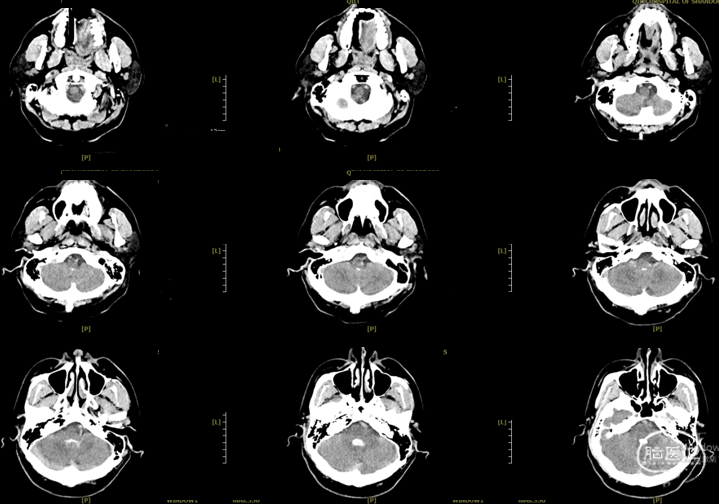

辅助检查:头胸部CT平扫2026-03-14我院脑出血并破入脑室,请结合临床复查,蛛网膜下腔出血。双肺少许纤维灶,双肺坠积性改变,请结合临床隔期复查,双肺少许小结节,考虑低危结节可能,建议结合临床年度随诊复查双肺部分小叶间隔增厚,肺水肿不除外,建议结合临床短期复查,冠脉壁钙化灶,胆囊结石。头颈部CTA2026-03-14我院颅内动脉轻度粥样硬化性改变,左侧优势型椎动脉,椎基底动脉迂曲延长。

初步诊断:1. 左侧额、岛叶、基底节脑出血破入脑室动静脉畸形?2. 脑疝;3. 高血压病3级(极高危)?4. 肺炎;5. 肺结节;6. 胆囊结石;7. 肺水肿;8. 脑动脉粥样硬化。